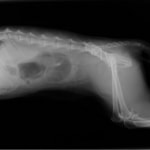

症例3:キルシュナーワイヤーのピンニングによる整復

ペルシャ猫 11ヶ月齢 雄

他院にて左大腿骨遠位の成長板骨折(salter-harrisⅠ型)が認められており、治療相談を目的として来院。当院にて、キルシュナーワイヤーを用いたピンニングにより骨折部位の整復を行いました。術後の経過は良好で、現在も経過観察中です。